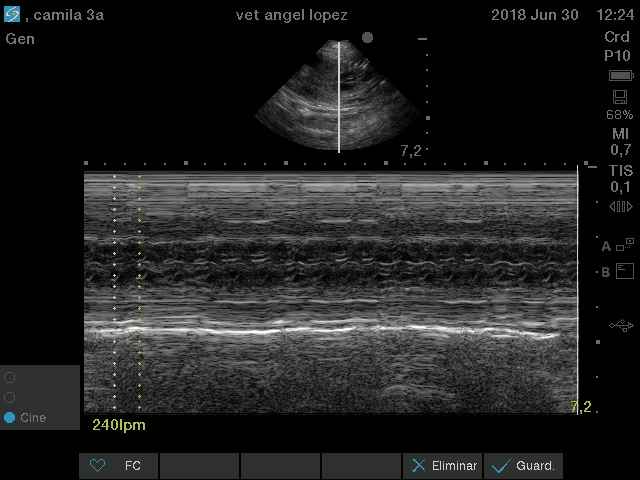

ecocardiografia basica